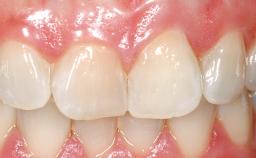

A 39-year-old male patient presented with a chief complaint of discomfort and gingival discoloration around his maxillary left central incisor. He was in good general health and was a non-smoker. His past dental history was significant because of the traumatic fracture of tooth 21 in a sporting accident at age 13. Initial dental treatment included endodontic therapy and a full-coverage restoration. The patient became symptomatic 5 years later, when structural failure of the tooth resulted in the dislodgment of the crown. Endodontic retreatment, apical surgery, and post-and-core restoration were performed.

Soft Tissue Anatomy Intact Defective